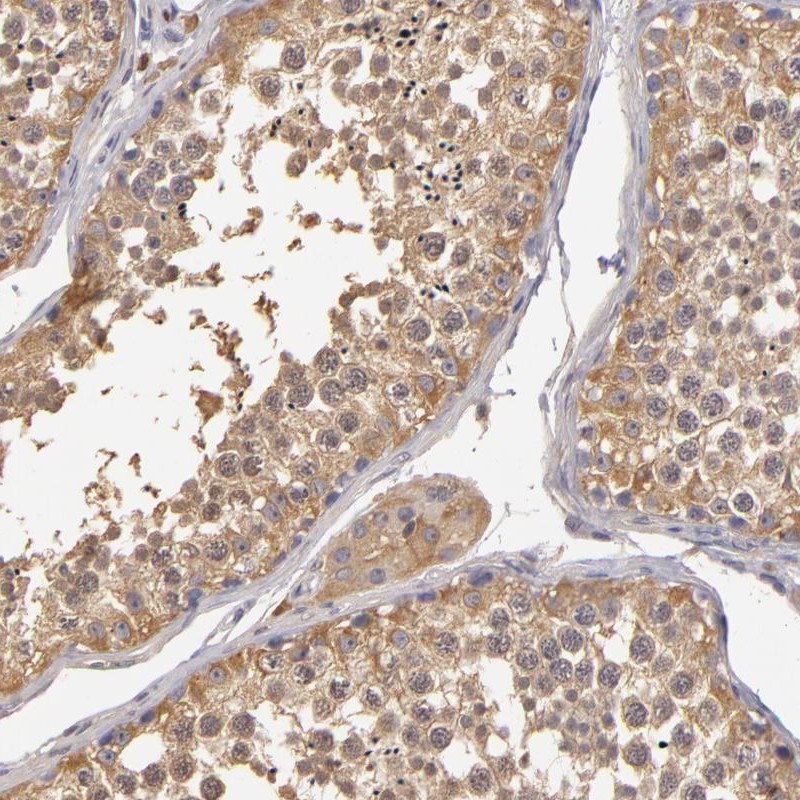

Immunohistochemical staining of human testis shows moderate cytoplasmic positivity in germ cells.